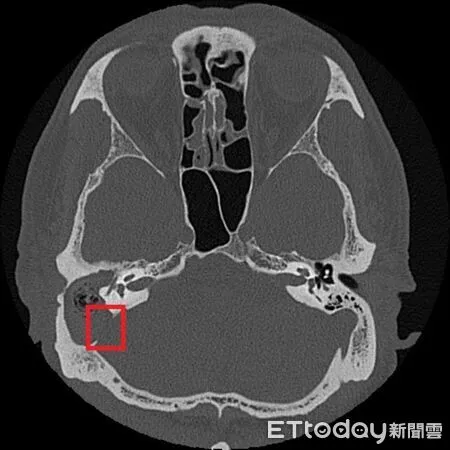

▲從張先生的影像可看到與後顱窩相隔的骨板遭膽脂瘤侵蝕(紅框處)。(圖/台北慈院提供)

鄭靜雯表示,經顳骨電腦斷層檢查後,確認為慢性中耳炎併發膽脂瘤,且已侵蝕顱底骨質,需立即住院,並以抗生素控制感染,待發炎情形穩定再安排手術,先打開乳突骨,完整清除病變組織,並同步進行鼓室重建、外耳道成形及顱底缺損修補,術後恢復良好。